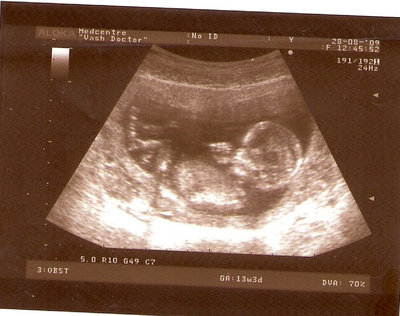

13 НЕД И 5 ДНЕЙ

| Вложения: |

3.jpg [ 96.81 КБ | Просмотров: 2435 ]

Nikisa писал(а): Foto prosto chudesnoe. A na kakom sroke uznali, chto sin.............. НА 13 НЕДЕЛЯХ.КАК РАЗ ВОТ В ЭТО узи, ОНО УМЕНЯ ВТОРОЕ БЫЛО. ЭТО КОНЕЧНО МАЛЕНЬКИЙ СРОК ДЛЯ ОПРЕДЕЛЕНИЯ ПОЛА. НО Я ПОПРОСИЛА ВРАЧА(ЭТО КТСТАТИВ РОССИИ БЫЛО) ХОТЯ БЫ ПРЕДПОЛОЖИТЬ. ЕЙ ВСЁ ТАКИ УДАЛОСЬ РАССМОТРЕТЬ.НУ ВООБЩЕМ ЧЕРЕЗ НЕСКОЛЬ ДНЕЙ ПОЙДУ К ВРАЧУ, УЖЕ АМЕРЕКАНСКОМУ И УЗНАЮ ТОЧНО. К ТОМУ ВРЕМЕНИ У МЕНЯ БУДЕТ СРОК 18 НЕДЕЛЬ. ХОТЕЛОСЬ БЫ ПОСМОТРЕТЬ НА ДРУГИЕ ФОТО НА ЭТОМ СРОКЕ ИЛИ БОЛЬШЕ. ТАК ЧТО ВЫКЛАДЫВАЙТЕ, ЕСЛИ НЕ ЖАЛКО!